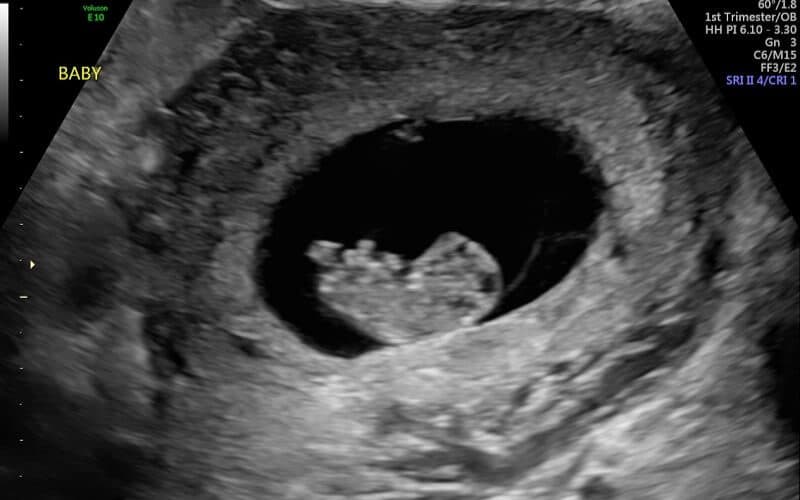

Để hình dung về phát triển của thai nhi 9 tuần tuổi, mẹ có thể ước lượng kích thước bé lúc này dài khoảng 2.2 – 2.5cm. Ở mốc thời gian này, kích thước của bé nhỏ xinh tương đương một quả nho hoặc một quả ô liu xanh và có những phát triển nhất định từ cả bên trong lẫn bên ngoài.

Thai nhi đang bắt đầu có những sự thay đổi rõ rệt mà khi khám thai mẹ có thể nhìn thấy. Sự phát triển bên trong của bé đang diễn ra với tốc độ chóng mặt. Dưới đây là những cột mốc hoàn thiện quan trọng của các cơ quan:

- Trái tim của bé đã hoàn thiện việc chia thành 4 buồng tim và đập nhanh gấp đôi so với nhịp tim của người lớn.

- Tất cả các cơ quan nội tạng thiết yếu như não, phổi, thận, gan và ruột đều đang hình thành và phát triển mạnh mẽ.

- Bắt đầu sự hình thành các bắp cơ, cho phép tay và chân bé có những cử động tự phát đầu tiên, đồng thời xương ở thai nhi cũng đang bắt đầu hình thành.

- Nằm sâu bên trong nướu, các mầm răng nhỏ hình củ đang phát triển để tạo nền tảng cho hệ răng sữa sau này.

1.2. Sự phát triển hình thái bên ngoài của thai nhi 9 tuần

Nếu mẹ thắc mắc hình dáng bên ngoài của em bé 9 tuần phát triển như thế nào, thì đây là lúc bé bắt đầu có những nét hình thái cụ thể:

- Đuôi phôi thai ở phần cuối tủy sống đã gần như biến mất hoàn toàn.

- Khuôn mặt bé dần rõ nét hơn, các bộ phận như môi trên, mũi, mí mắt đã hình thành. Lưỡi bé lúc này bắt đầu hình thành chức năng vị giác và khu mắt bé đang to ra, bắt đầu có một chút sắc tố màu.

- Tay và chân của thai nhi lúc này đang dần dài ra và cân đối hơn với cơ thể. Tay bé đã có thể gập ở khuỷu và đủ dài để đặt vắt ngang lên ngực.

- Các khớp gối, cổ tay, cổ chân đã phát triển, đồng thời các ngón tay và ngón chân có thể được nhìn thấy qua siêu âm.

- Cơ quan sinh dục bé đang bắt đầu định hình, tuy nhiên lúc này vẫn chưa thể xác định chính xác giới tính của thai nhi qua siêu âm.

3. Thai 9 tuần cần siêu âm và kiểm tra gì?

Khi khám thai ở thời điểm này, mẹ bầu được kiểm tra chiều cao, cân nặng, nhịp tim, siêu âm đánh giá các chỉ số phát triển của thai nhi theo mốc thai.

Ở tuần thứ 9, mẹ vẫn đang nằm trong giai đoạn lý tưởng (từ tuần 8 đến tuần 14) để thực hiện siêu âm xác định chính xác tuổi thai và dự đoán ngày sinh nở. Ngoài ra, từ tuần thứ 10 trở đi, mẹ đã có thể trao đổi với bác sĩ về việc thực hiện xét nghiệm tiền sản không xâm lấn (NIPT) nhằm tầm soát các bất thường về nhiễm sắc thể từ sớm.